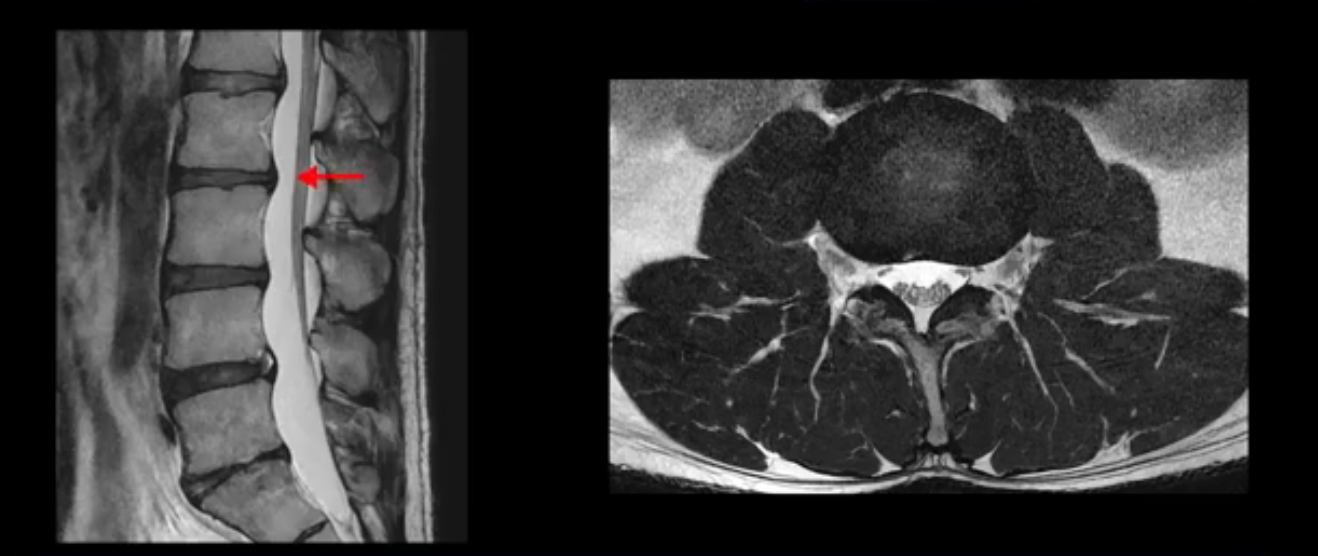

4번 5번은 가운데로 섬유륜이 찢어져서 디스크가 살짝 밀려나와 있지만 역시나 최근에 찢어지고 밀려나온 걸로 판단되지 않고 오래 전에 찢어진 흔적으로 보입니다.

왜 최근에 찢어진 급성이 아니고 오래된 거라고 하는지 이 부분도 뒤에 한꺼번에 설명 드리겠습니다.

앞서 1번 2번, 4번 5번, 5번 1번의 디스크가 찢어지고 조금 밀려 나온 게 최근에 찢어진 게 아니고 오래된 걸로 보인다고 말씀 드렸죠. 왜 그럴까요? 만약 급성으로 찢어진 것이라면 아주 심한 디스크성 통증이 있겠죠. 기침이나 재채기를 하면 심하게 아프고 허리를 조금만 구부리거나 비틀면 아주 날카로운 통증들이 생길 겁니다. 그런데 이분은 이런 증상이 전혀 아닙니다. 또 디스크의 밀려나온 정도도 전혀 심하지 않기 때문에 이분이 가지고 계신 양쪽 다리 저림, 특히 이분은 누워있을 때도 양쪽 발이 발가락까지 쑤신다고 하는데 이정도 디스크 때문에 그런 증상은 생길 수가 없는 겁니다. 이처럼 이분의 가벼운 디스크 탈출은 이미 오래 전에 진행되었고 섬유륜 자체는 이미 아문 상태인데도 디스크내장증을 진단받은 환자들 중에는 본인이 섬유륜 파열 환자라고 끝까지 믿는 분들이 많습니다. 다시 말하지만 디스크내장증이라는 진단을 받은 환자들을 보면 거의 전부 다 섬유륜 파열 증상이 아닙니다. 증상이 완전히 다릅니다. 진단이 애초에 잘못되면 어떤 치료를 받아도 좋아질 수 없습니다.

이분은 어떤 한 병원에서 디스크 내장증 얘기를 들으셨는데요. 여기 보시는 것처럼 4번 5번의 하얀 HIZ(High Intensity Zone)을 보고 디스크 내장증의 근거로 얘기하는 병원들이 있는데,

이 HIZ는 섬유륜이 찢어졌다가 이미 아문 뒤에도 얼마든지 보일 수 있는 흔적일 가능성이 있어서 재채기를 하면 아픈지, 허리를 구부릴 때 날카로운 통증이 생기는가 등의 증상으로 구별해야 하는데 MRI만 보고 HIZ가 보이면 그게 마치 통증의 원인인 것처럼 얘기하는 의사들이 있습니다. 이분 MRI를 자세히 보고 증상을 정말 자세히 들어본 의사가 있었더라면 다른 환자분들처럼 증상과 MRI가 일치하지 않는다는 얘기를 들을 수 있었을 텐데 이분은 그런 얘기는 듣지 못했습니다.